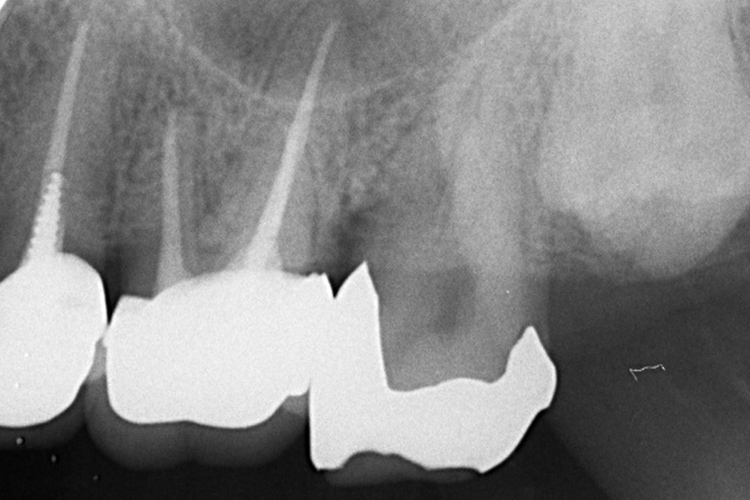

実施例②

この患者様は、スケーリングより歯周ポケットが6mm以上ある患者様で、ご本人も歯周病になりかけている自覚がありました。また、口臭も気になされていましたので、ブルーラジカルの適用症例と判断し、施術を行いました。

実施前

施術前のレントゲンと口腔内写真です。